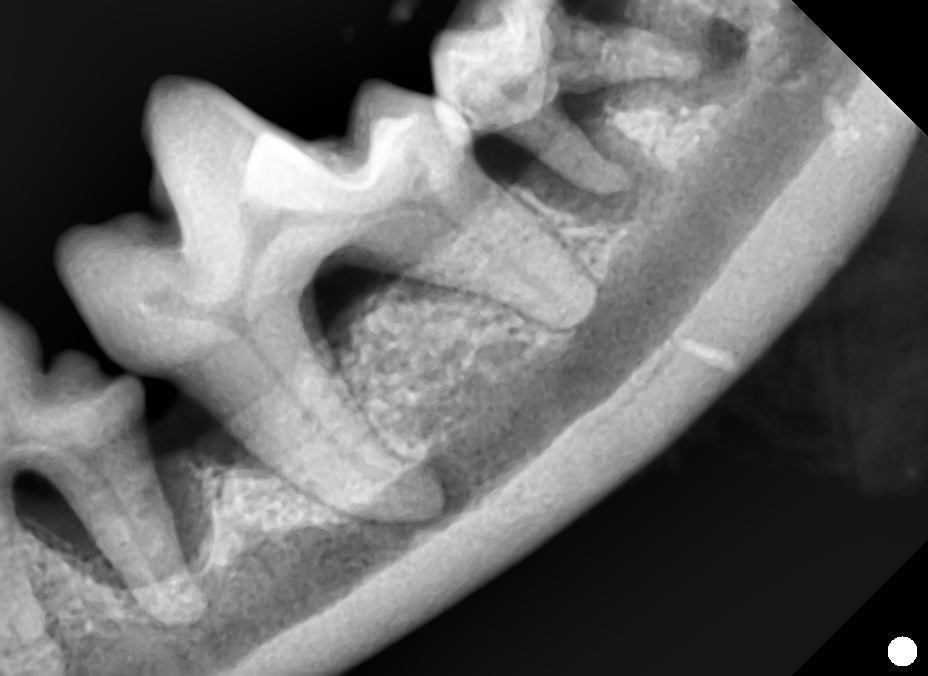

今回の患者さんは、重度の歯周病による下顎第一後臼歯の骨融解を認めたケースです。

レントゲン検査では3壁性の垂直性-水平性骨欠損を確認しました。

処置は全身麻酔下で行い、M-MINSTの手技により歯周ポケット底部まで根面清掃を徹底。骨欠損部には自己由来PRFを充填し、歯周組織の再生を促進しました。